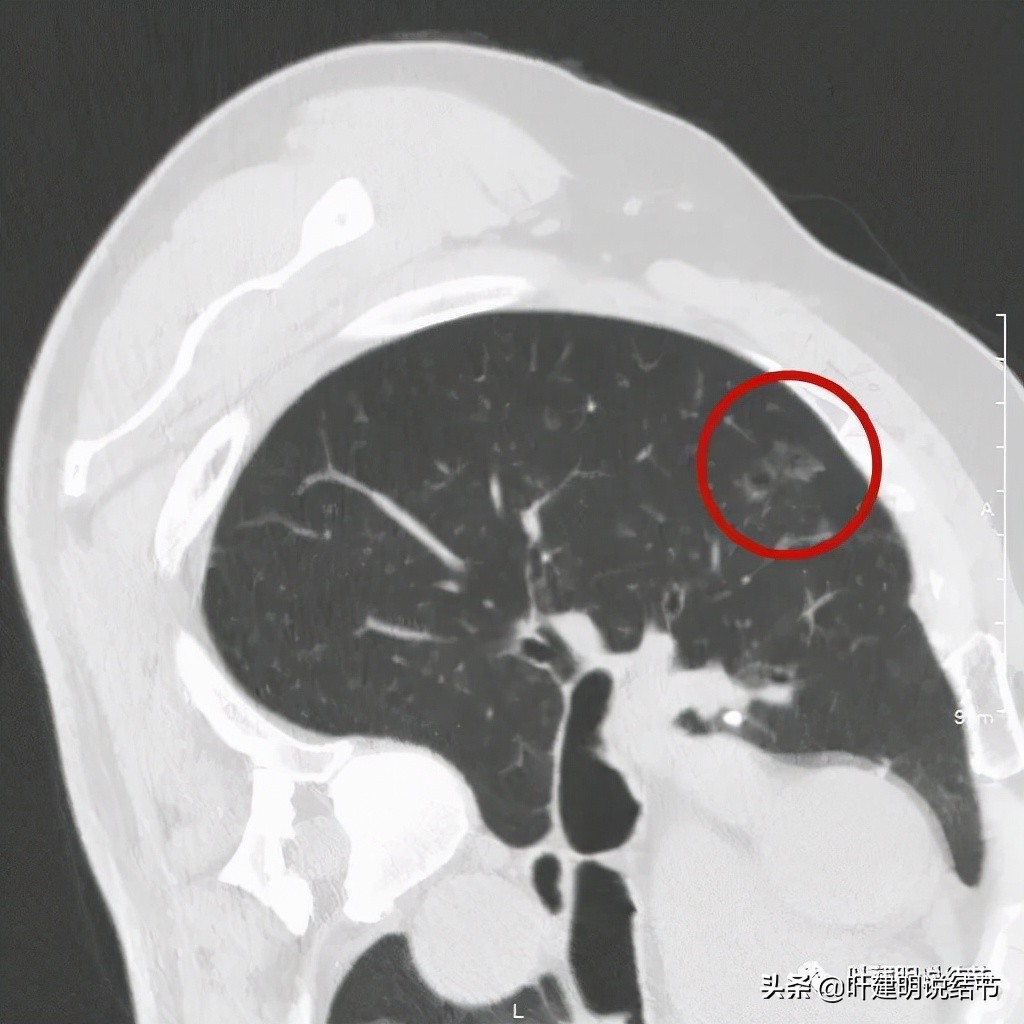

以上诸图是病灶4:考虑囊腔型肺癌可能性大,壁厚薄不均,内壁不光滑,有血管进入病灶,有少许密度偏高的成分,但纵隔窗上未见,不是真正意义上的实性成分。